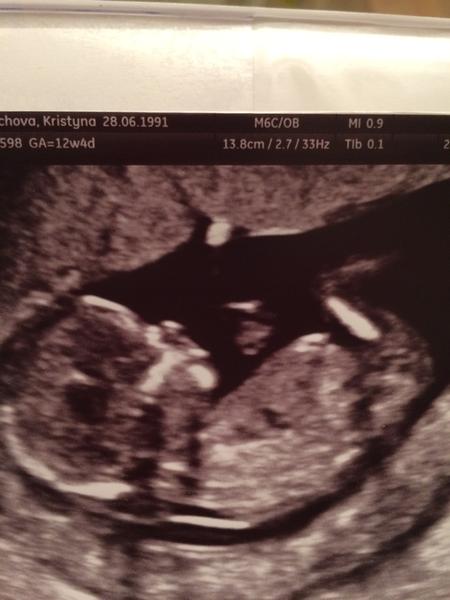

Tak tohle už snad nemůže být jasnější 😀 Kluk jako vyšitý 👍

@janyshka u @mariejosef je to teda holccicka jak vysita. po dvou klucich jsem mela uplne stejny UTZ a ted uz s braskama spi doma skoro rocni slecna 🙂

@mariejosef myslím ten první obrázek, který zahájil diskuzi. ...